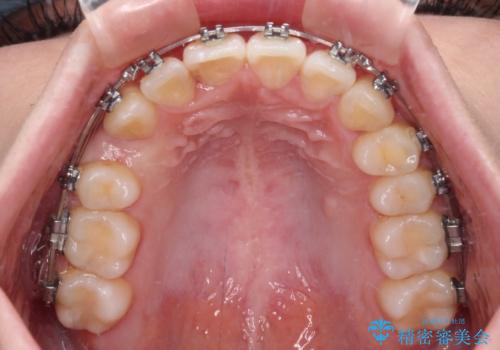

- メタルブラケット

- 1年5ヶ月

お仕事の予定を調整しやすく、平日の昼の時間帯に通院可能であったので、非常にスムーズに治療を進めることができ、1年半で無事に治療を終えることができました。